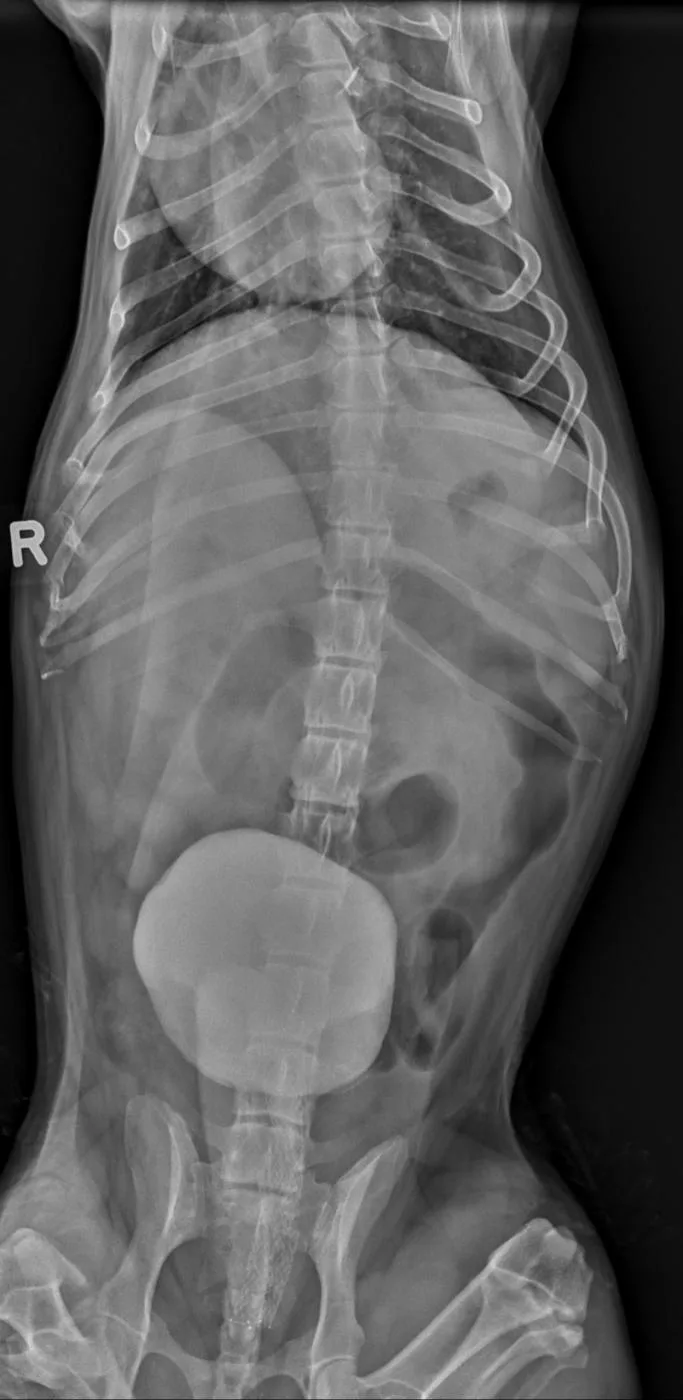

Figure 12A Dog after urethral stent placed to alleviate a complete urinary obstruction secondary to prostatic carcinoma

This 2-view contrast urethrogram shows a 12-year-old neutered male miniature schnauzer just after urethral stent placement for alleviation of a complete urinary obstruction secondary to prostatic carcinoma. The urinary bladder is cranially displaced and moderately distended with radiopaque contrast media. Visible in the left lateral view (Figure 12B), a large, round soft tissue mass caudal to the contrast-filled bladder is consistent with a prostatic mass. A metallic stent (Figure 12B; arrows) spans the entire length of the prostatic urethra and extends a short distance into the trigone of the urinary bladder. The enlarged prostate has caused left lateral displacement of the descending colon. The patient appeared to urinate comfortably immediately after stent placement.